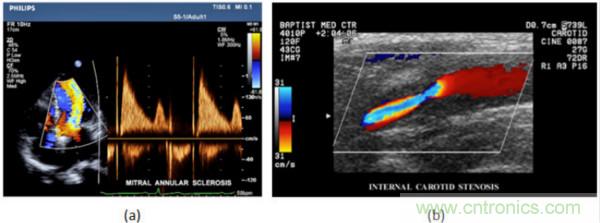

在CW和PW多普勒模式中,流信息是從一個聚焦聲束中獲得的,類似于A模式成像。在20世紀(jì)80年代,研究人員基于彩色多普勒技術(shù)完成了血流分布的二維信息可視化。彩色多普勒處理也是基于B模式/PW模式信號路徑。從感興趣區(qū)域收集多幀RF數(shù)據(jù)。由于感興趣區(qū)域中的血液流動導(dǎo)致圖像幀之間存在數(shù)據(jù)差異。相域中的自相關(guān)和時域中的互相關(guān)兩種算法可從RF數(shù)據(jù)中提取數(shù)據(jù)方差(即血流速度和方向信息):。根據(jù)預(yù)定義的顏色漸變條相應(yīng)地映射包括速度和方向的血流信息。通常,藍(lán)色和紅色代碼分別識別朝向和遠(yuǎn)離換能器移動的血流。當(dāng)流速增加時使用更亮的顏色,反之亦然。顏色映射的2D分布始終疊加在B模式圖像上,以實時同時顯示個體解剖結(jié)構(gòu)和血流。它對于診斷心血管疾病,如血管閉塞和心臟瓣膜反流,極其有用。典型的彩色多普勒圖像如下圖所示,(b)顯示頸動脈狹窄引起的血流流速變化。

圖7.彩色多普勒成像:(a)以彩色多普勒和CW模式獲得的圖像(由Philips提供); (b)顯示頸動脈狹窄的彩色多普勒(由GE提供)